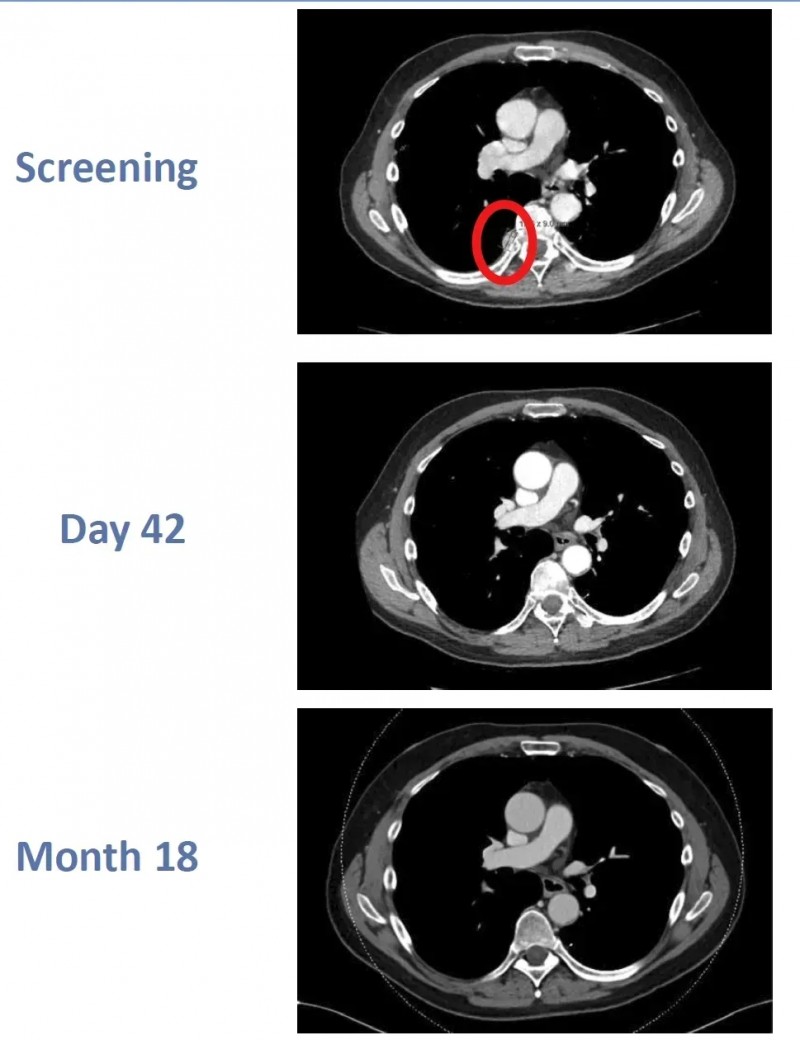

在第37届癌症免疫治疗学会年会(SITC)上,一则CTX130 CAR-T细胞治疗透明细胞肾细胞癌(RCC)的案例引发关注——患者成功实现持久完全缓解(CR),疗效惊艳!

该案例中的64岁男性患者,确诊透明细胞肾细胞癌后,虽接受过阿替珠单抗联合卡博替尼治疗,但病情仍复发且癌细胞转移至肺部和胸膜。随后,患者入组CTX130治疗肾细胞癌的1期临床试验(NCT04438083)。

治疗结果超出预期:患者接受CTX130治疗后先达到部分缓解(PR),治疗第3个月更奇迹般实现完全缓解(CR);至治疗第18个月复查时,完全缓解状态仍持续维持。这也是异基因CAR-T细胞治疗在肾癌领域首次达成如此持久的完全缓解,为晚期肾癌治疗带来新突破。

▲图源“BMJ”,版权归原作者所有,如无意中侵犯了知识产权,请联系我们删除